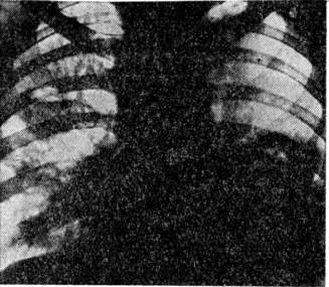

Лимфатических, узлы обычно увеличены незначительно, между собой не спаяны, эластической консистенции, серо-розового цвета, иногда с мелкоточечными кровоизлияниями. В некоторых случаях выявляется увеличение миндалин, лимфатических, фолликулов и пейеровых бляшек с наличием очаговых некрозов и изъязвлений, однако такие изменения встречаются значительно реже, чем при острых Лейкозы. Лёгкие нередко увеличены в объёме, сероватого цвета, под плеврой и в толще лёгочной ткани определяется мелкопетлистая сеть сосудов, часто встречаются участки пневмонии.

При микроскопическом исследовании в костном мозге преобладают незрелые и зрелые клетки гранулоцитарного ряда (рисунок 5), соотношение которых может варьировать. По данным трепанобиопсий, в начальной стадии заболевания ещё в достаточном количестве сохраняются элементы эритропоэтического и мегакариоцитарного ряда. По мере прогрессирования процесса их число снижается, исчезают жировые клетки. Характерны глубокие изменения в строме в виде сочетания процессов деструкции с увеличением количества фибробластов, аргирофильных и иногда коллагеновых волокон. Изучение костного мозга методом трепанобиопсии в динамике свидетельствует о том, что миелофиброз постепенно нарастает и бывает более выражен у больных с повторными ремиссиями и обострениями заболевания. В отдельных случаях в костном мозге имеют место обширные очаги некроза; постоянно наблюдается выраженное рассасывание костной ткани. В селезёнке и лимфатических узлах в развёрнутой стадии болезни обнаруживается диффузная инфильтрация миелоидными элементами, атрофия лимфатической ткани. Лейкозное поражение селезёнки часто сопровождается выраженным в различной степени фиброзом красной пульпы, образованием полей склероза, что наряду с инфильтрацией и полнокровием является причиной увеличения её веса. Для хронический миелолейкоза характерна локализация лейкозных инфильтратов в печени по ходу синусоидных капилляров (рисунок 6), в лёгких — в области межальвеолярных перегородок. Нередко наблюдается инфильтрация стенок мелких бронхов, сосудов, плевры. Реже, чем при острых Лейкозы очаги лейкозной инфильтрации возникают в почках, мышце сердца, в стенках желудочно-кишечные тракта, в оболочках и веществе головного мозга, коже, железах внутренней секреции и других органах.

Острый лимфобластный лейкоз, особенно у детей, чаще всего характеризуется массивным поражением всех групп лимфатических, узлов, селезёнки, вилочковой железы, нередко со значительным их увеличением. В вилочковой железе лейкозная инфильтрация располагается внутри долек и обусловливает разрушение эпителиального ретикулума. В лёгких разрастания локализуются преимущественно в стенках и окружности бронхов, в печени — в области портальных полей. При распространённом процессе пролифераты выявляются в желудочно-кишечные тракте, центральная нервная система, почках, половых органах и другие В детском и юношеском возрасте обширные узловатые разрастания чаще возникают при данной форме и локализуются главным образом в вилочковой железе и лимфатических, узлах переднего средостения. Нередко они распространяются на перикард, плевру, ткань лёгких, что приводит к образованию массивного опухолевого конгломерата. Разрастания в костном мозге и других органах состоят из бластных клеток лимфоидного происхождения, которым свойственно высокое ядерно-цитоплазматическое соотношение.